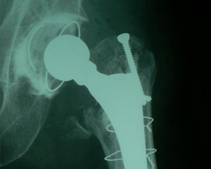

Женщине, которая сломала шейку бедра, установили протез тазобедренного сустава.

Вы знаете, такой перелом обычно считается началом конца. Но установленный нашими специалистами протез позволяет пациенту вести нормальный образ жизни, – подчеркнул Сергей Рыженко.

Руководил операцией доктор медицинских наук, профессор Александр Лоскутов, которого называют одним из пионеров современного эндопротезирования в Украине.